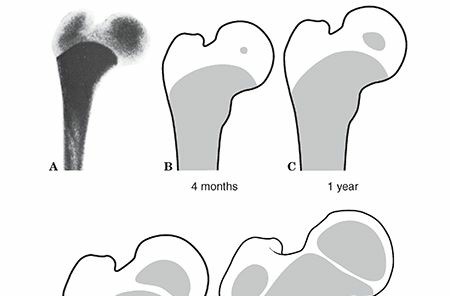

PEDIATRIC HIP PEDIATRIC HIP FRACTURES Epidemiology Hip fractures are rare in children, occurring less than 1%…